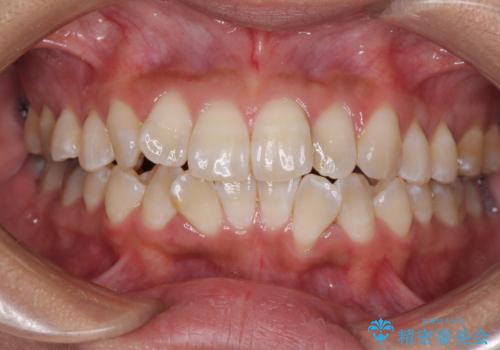

【ワイヤー矯正】八重歯 歯のでこぼこを治したい!